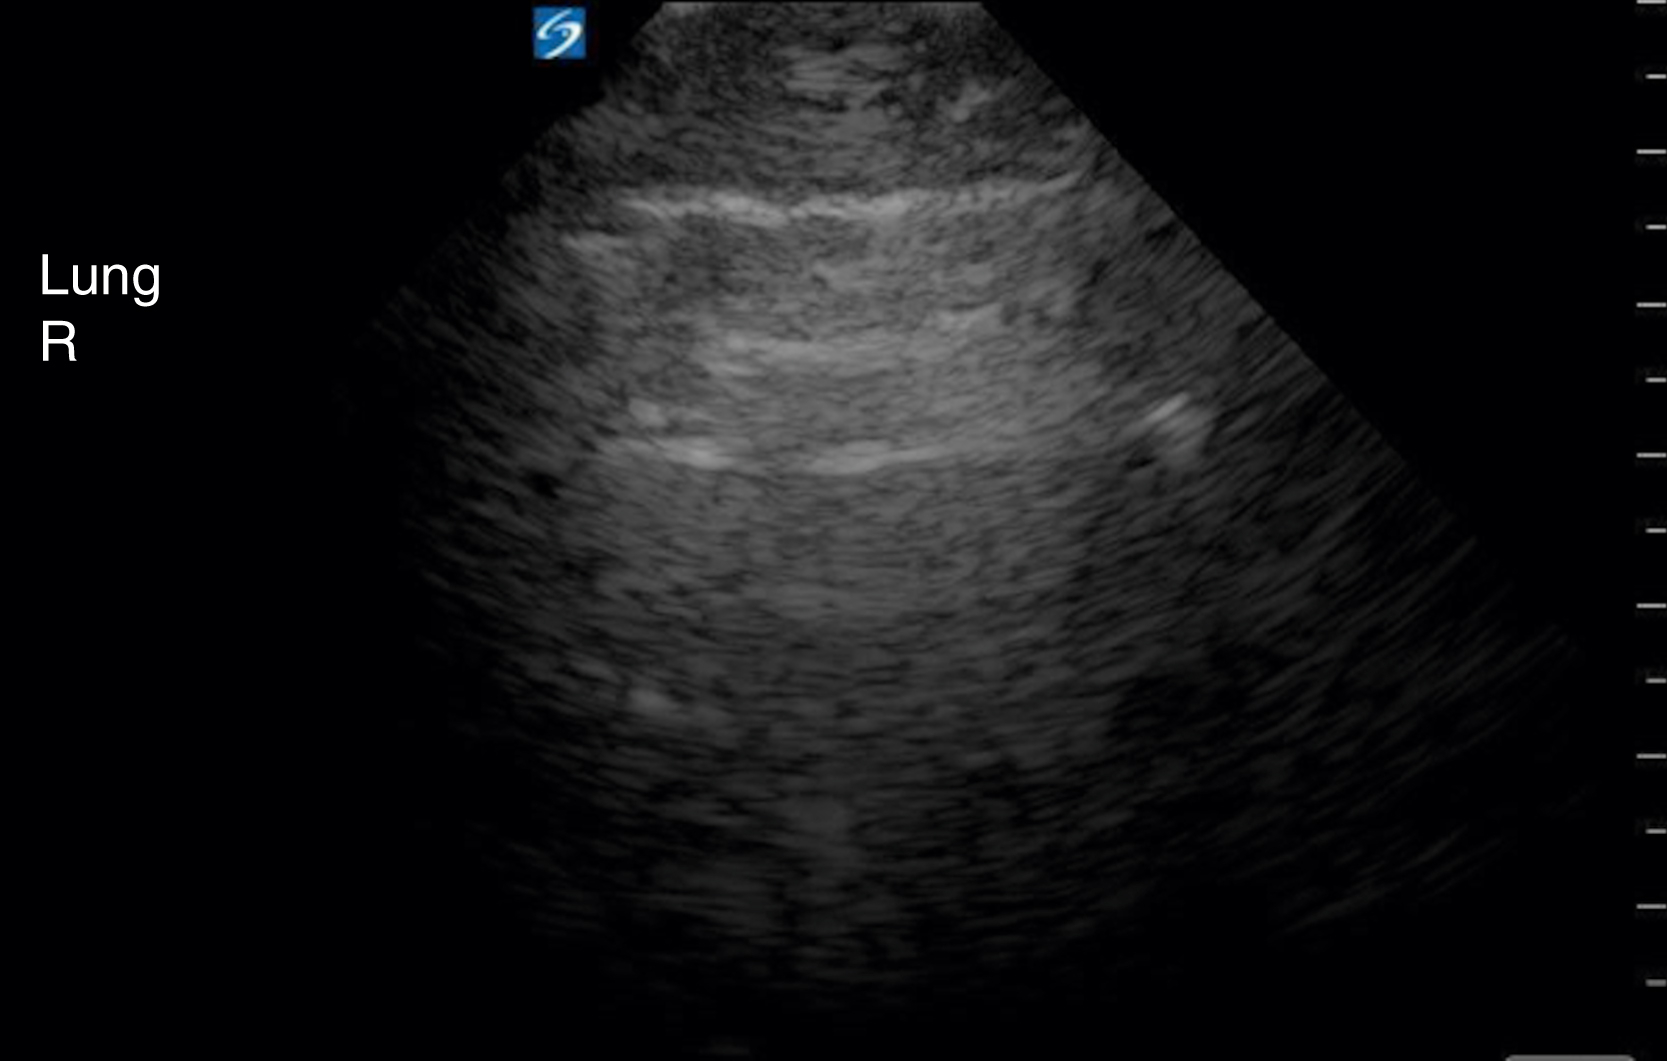

Thoracic US is often performed with a low-frequency curvilinear array or phased array transducer, although visualization of lung sliding may be enhanced, if necessary, by the use of a high-frequency linear array transducer. The original BLUE (Bedside Lung Ultrasound in Emergency) protocol evaluated 4 areas on each hemithorax, but subsequent studies have looked at a number of protocols and additional areas of the anterior, lateral, and posterior thorax. Lung sliding, a normal finding, is identified as the visceral and parietal pleura gliding against each other during normal respiration. A lines, horizontal equally spaced echogenic artifacts deep to the pleural line, are also a normal finding ( Fig. e3.14 ).

Fig. e3.14

A lines signifying normal lung.